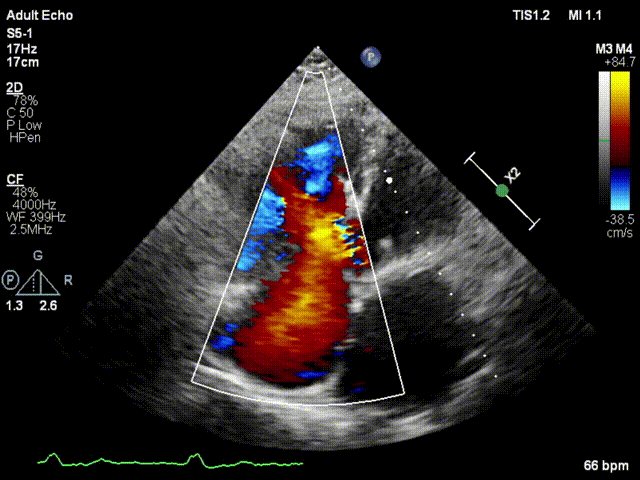

本次接受治療的患者是一名74歲的女性,14年前因風(fēng)濕性心臟病行二尖瓣生物瓣植入術(shù),合并房顫。近3年來(lái)反復(fù)因腹脹、納差、下肢水腫入院,藥物治療欠佳。心臟超聲顯示三尖瓣極重度反流(有效反流口面積:0.76cm²,反流容積:79ml),繼發(fā)性右房室增大及上、下腔靜脈增寬(右房上下徑*左右徑:52*41mm,右室左右徑:46mm,下腔靜脈:29mm),右室收縮功能正常,肺動(dòng)脈收縮壓 43mmHg,左心室射血分?jǐn)?shù)73% 。患者既往開胸手術(shù)史,術(shù)前評(píng)估STS 評(píng)分為7.02分,CRS 9分,無(wú)法接受體外循環(huán)下三尖瓣外科手術(shù)。面對(duì)這一傳統(tǒng)治療無(wú)法解決的困境,葛均波院士及其團(tuán)隊(duì)周達(dá)新教授、潘文志教授、張?jiān)床┦俊㈥惿┦考靶某业呐舜湔浣淌凇⒗顐ソ淌诮?jīng)過(guò)討論決定,采用創(chuàng)新的Lux-Valve Plus系統(tǒng)為患者進(jìn)行經(jīng)血管三尖瓣置換。

手術(shù)在患者全麻狀態(tài)下進(jìn)行,采用經(jīng)右側(cè)頸靜脈作為入路,將裝載有人工瓣膜的輸送器緩慢推送至右心房;并在經(jīng)食道超聲和DSA的引導(dǎo)下小心調(diào)整輸送器角度,將輸送器送入右心室;逐步釋放瓣膜錨定裝置和盤片,調(diào)整瓣膜位置后,錨定瓣膜完成植入。術(shù)后右房壓明顯下降,從術(shù)前的25/10(16) mmHg降至術(shù)后即刻的12/7(10) mmHg,術(shù)后超聲提示人工三尖瓣同軸性良好,固定牢固,無(wú)反流及瓣周漏,手術(shù)室即刻拔除氣管插管。